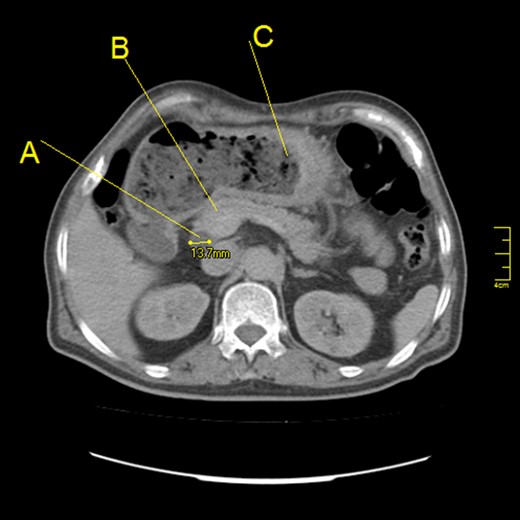

Intravenous contrast computed tomography showed thickening of proximal gastric and pyloric walls and a mild dilatation of extra- and intra-hepatic bile ducts, although the head of pancreas was normal (Fig. 2).

Abdominal computed tomography scan (axial section) showing: (A) Dilatation of common bile duct (a diameter of 13.7 mm). (B) Normal head of pancreas. (C) Thickening of greater curvature with a high amount of residual food.